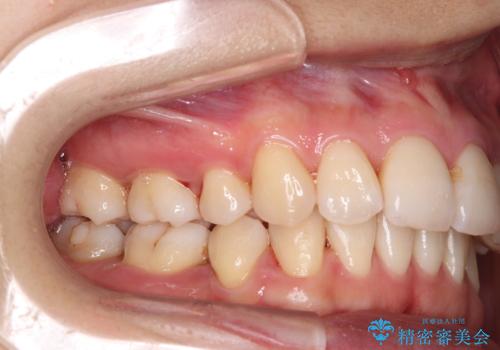

[ 奥歯の歯周病 ] エムドゲインを用いた再生治療